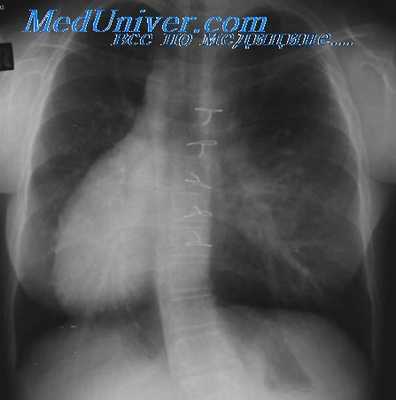

На рентгенограммах в прямой проекции на левом контуре сердца определяются две дуги: верхняя представлена часто наблюдающейся левосторонней дугой аорты и участком нисходящего отдела аорты, нижняя образована выходящим па левый контур ЛП. Дуга легочной артерии отсутствует. Правый контур сердца представляет собой сплошную выпуклую линию, простирающуюся от диафрагмы до основания сердца, которая образована вверху ПП и внизу ПЖ.

- Рентгенография ОГК. На рентгенограмме визуализируется смещение сердечной тени вправо, при комбинированных аномалиях изменяются контуры магистральных сосудов. Чтобы подтвердить транспозицию проводится рентгенография органов брюшной полости.